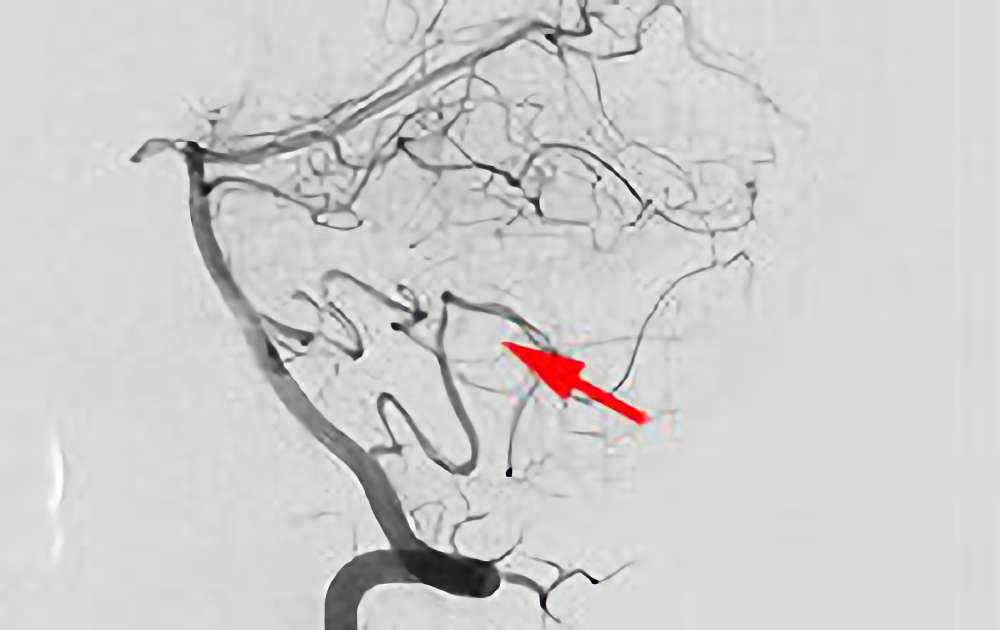

No.1585 手術前

No.1585 手術中

No.1585 手術後